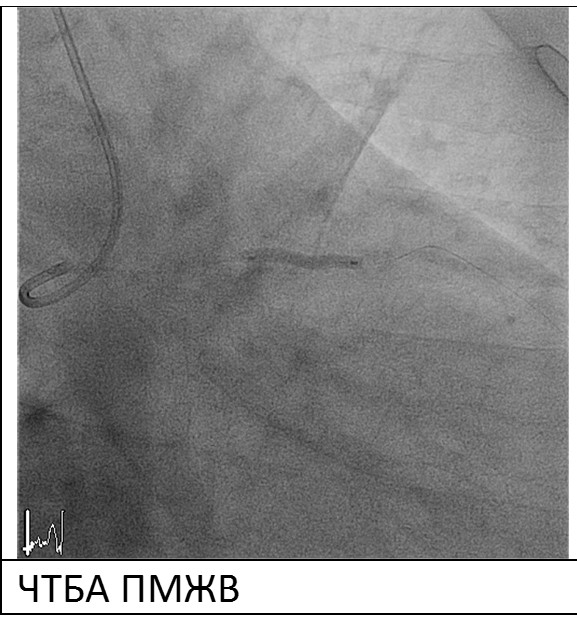

Решено выполнить коронарное стентирование передней межжелудочковой артерии. Выполнена предилятация зоны поражения ПМЖВ баллонным катетером 2,5*20мм.

Обращает на себя внимание отсутствие хорошей поддержки проводникового катетера. В результате чего, при попытке проведения коронарного стента в зону поражения передней межжелудочковой артерии, произошла его дислокация и «потеря» проводника из истинного просвета ПМЖВ. Пациент тотчас же почувствовал сильный болевой приступ за грудиной, на ЭКГ мониторе - элевация сегментов ST. Неоднократные попытки катетеризировать ЛКА гайдом с большим «коленом» успехом не увенчались.